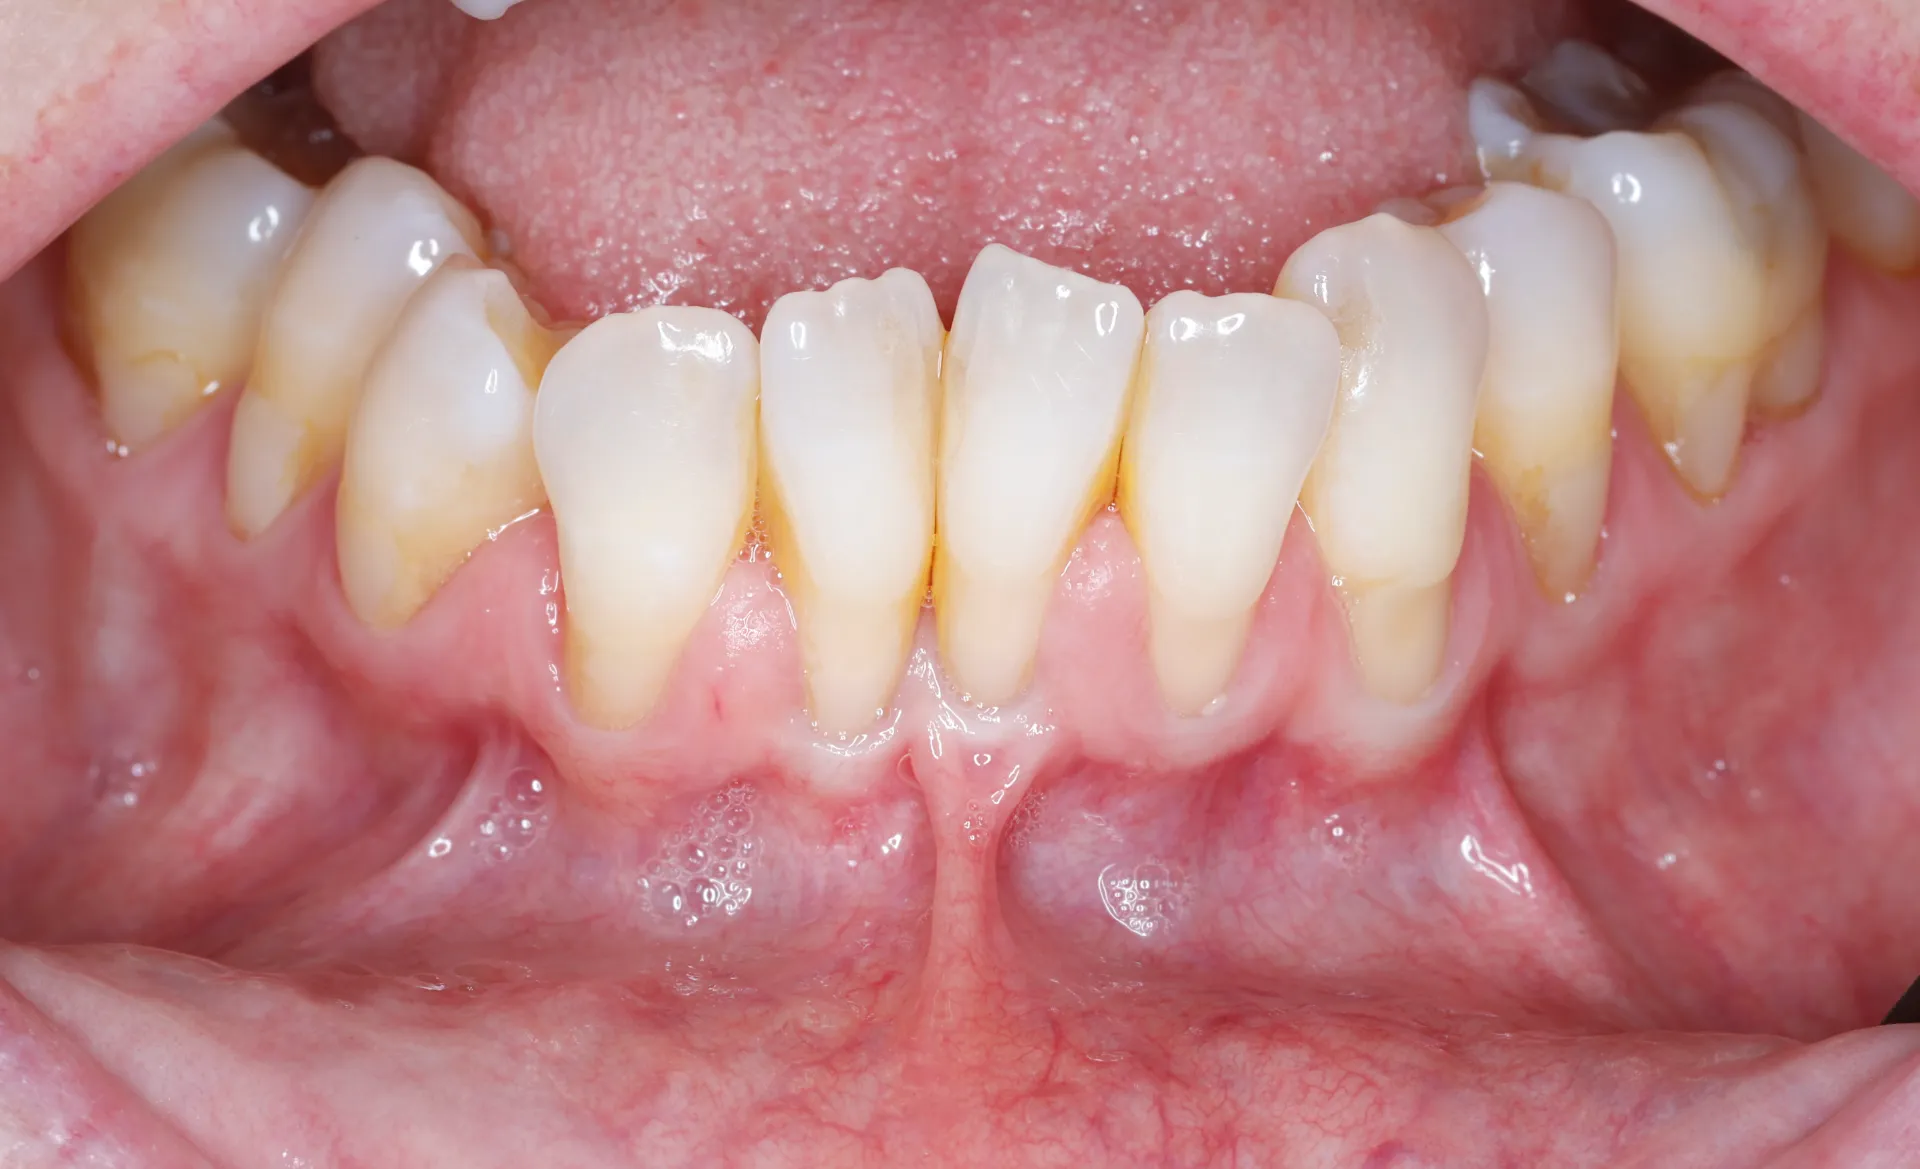

Gum Recession